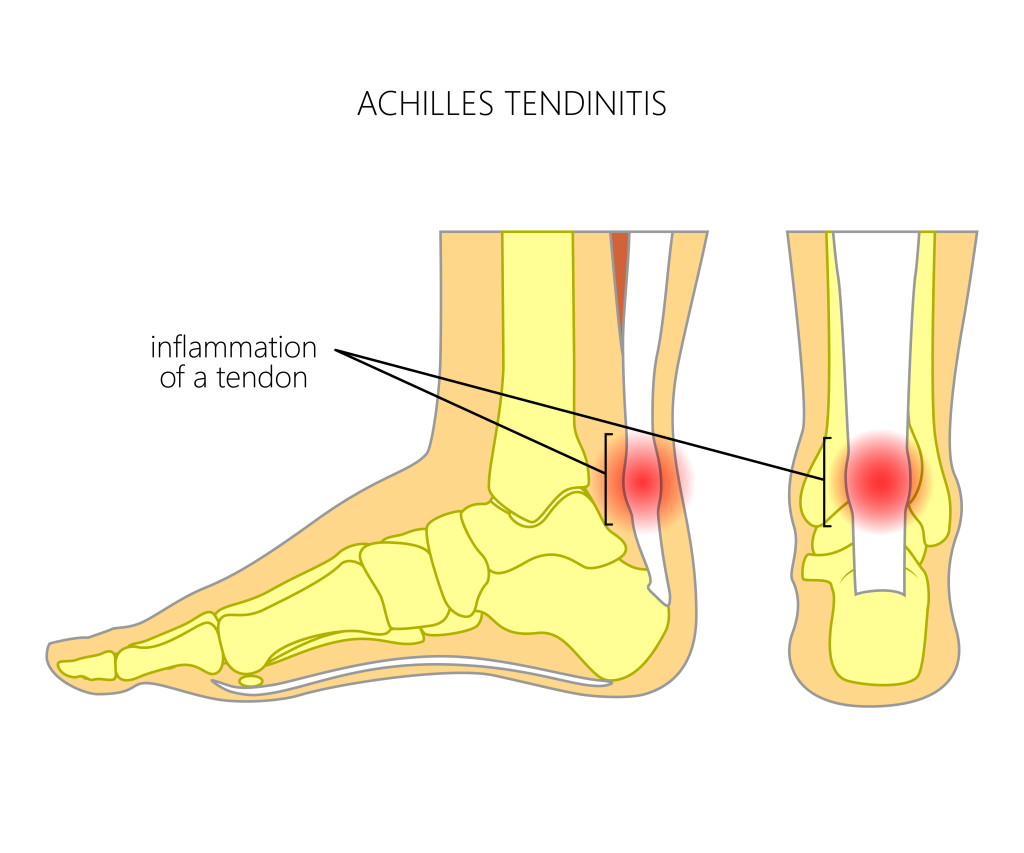

Achilles tendon injuries often cause pain, stiffness, and swelling in the back of your leg near your heel.

Using ice and resting may help, but you also want to keep your tendon from moving around too much. It mainly occurs in people playing recreational sports, but it can happen to anyone. Achilles tendinitis treatment includes rest, physical therapy and supportive shoes.

We show you only the best treatments for your condition and symptoms—all vetted by our medical team. She will make the correct diagnosis and develop an individualized treatment plan for your specific injury. Warmth around the heel or along the tendon difficulty standing on your toes thickening of the achilles tendon causes of achilles tendinitis